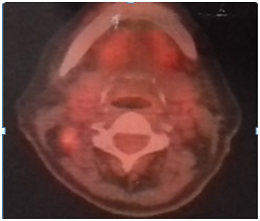

The patient underwent radical node dissection (45 lymph nodes), who’s biopsy revealed reactive histiocytosis. FNB of the thyroid lesion (Figure 2) depicted metastatic infiltration from the same ovarian carcinoma. After this diagnosis, a right lobe lobectomy was performed. FNA of the liver, under ultrasound guidance, indicated fatty liver and fibrosis with no signs of malignancy. Thyroid biopsy confirmed the diagnosis of malignant metastatic lesion 2x1, 5cm by the ovarian carcinoma (Figure 3,4). The 7 local lymph nodes were negative for infiltration from the neoplasm. The patient started chemotherapy with CDDP/Docetaxel with adjuvant intends, after 4 weeks, mainly to treat the potential mediastinal metastatic lymphadenopathy (we have no biopsy from this site at present).

Figure 2 Thyroid metastasis on U/S.